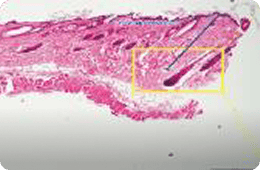

532 PS

침투깊이 : 861.15~1,229 μm

침투깊이 : 600.66~918.46 μm

출처 : A Randomized, Prospective, Split-Face Pilot Study to Evaluate the Safety and Efficacy of 532-nm and 1,064-nm

Picosecond Lasers Using a Diffractive Optical Element for Non-Ablative Skin Rejuvenation, Dermatologic Therapy, 2022

특히나 스컬피오의 532PS 핸드피스는 표피를 보존하면서

진피 내에서 LIOB를 생성하여 전통적인 532nm 레이저의 한계를 극복합니다.